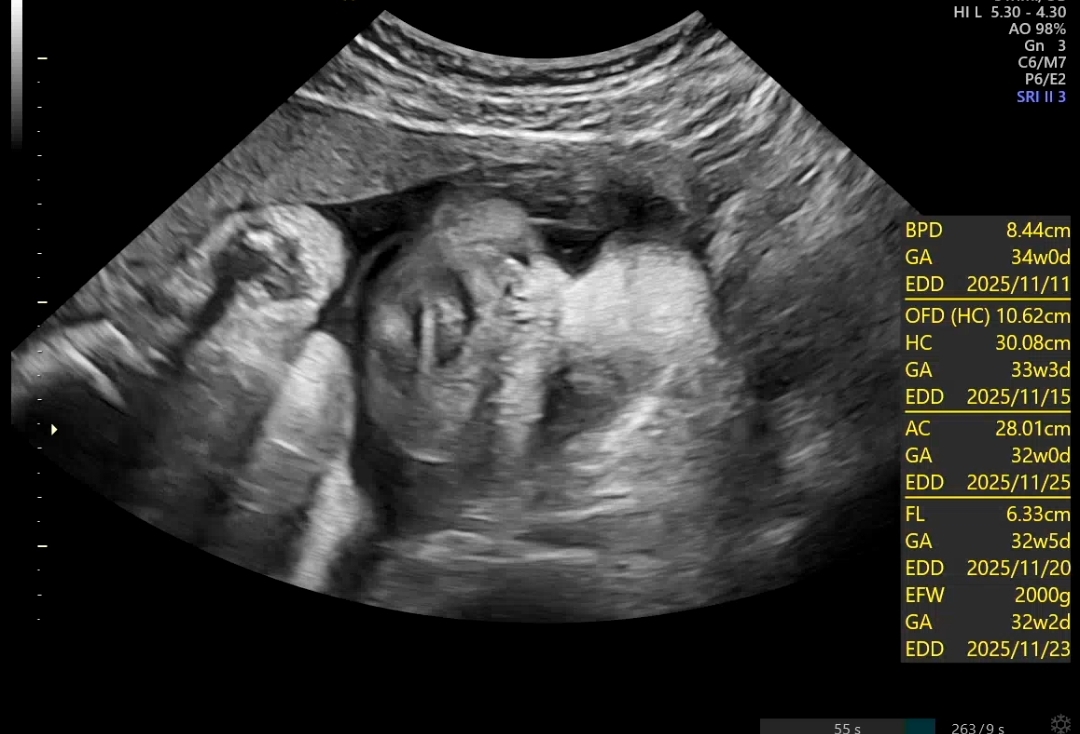

아주 잘크고 있는 만세 2키로 돌파..!!